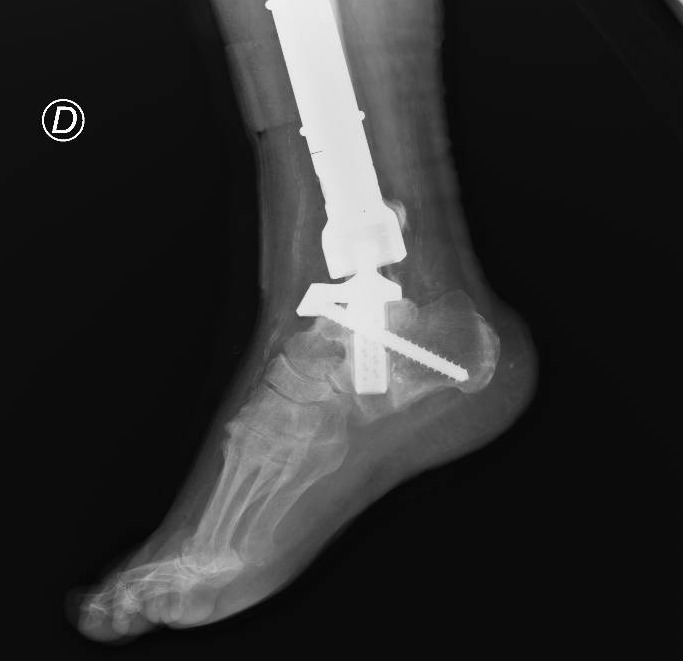

Il paziente veniva dunque trattato con una resezione del tumore con impianto di mega-protesi di tibia prossimale (cioè nell’area vicino al ginocchio). Ma i problemi non erano finiti. Dopo circa un anno dall’intervento, compariva una grave infezione della protesi impiantata e questo porta Mario a una serie di complessi interventi chirurgici, esitati con l’impianto di una protesi totale di gamba e di caviglia in titanio, rivestita in argento per proteggerlo dalle infezioni.

A distanza di sei anni, Mario torna dagli ortopedici del Gemelli per la comparsa di un dolore alla caviglia. Gli esami effettuati rivelano la rottura di una vite della protesi, a livello della caviglia. È necessario dunque sostituire questo pezzo, ma l’unico modo per farlo è facendo confezionare una protesi su misura (‘custom-made’). Gli ortopedici del Gemelli inviano la TAC di Mario all’Implantcast, una ditta specializzata di Buxtehude, una cittadina a sud ovest di Amburgo.

Basandosi sulla ricostruzione 3D della caviglia ‘bionica’ di Mario, i bioingegneri realizzano un “calco” della protesi custom-made con una stampante 3D, sul quale viene poi realizzata la protesi in titanio per l’impianto definitivo. Tutto è pronto per l’intervento al Gemelli che viene realizzato dal professor Carlo Perisano, professore aggregato dell’Università Cattolica del Sacro Cuore e dirigente medico presso la UOC di Ortopedia e Traumatologia di FPG, diretta dal professor Giulio Maccauro. Si tratta di un intervento unico nel suo genere, un esempio di come la medicina di precisione e personalizzata sia ormai entrata a far parte anche degli interventi chirurgici. Che dà i suoi frutti. A distanza di appena qualche giorno dall’intervento, Mario sta di nuovo in piedi sulla sua gamba ‘bionica’ arricchita di quest’ultimo gioiello tecnologico.

“Il paziente era stato sottoposto negli anni a diversi interventi chirurgici per il trattamento di un tumore osseo della tibia e delle successive complicanze che avevano compromesso anche le articolazioni del ginocchio e della caviglia – spiega il professor Perisano -. Nel 2019, è stato sottoposto a posizionamento di mega-protesi custom-made personalizzata di tibia totale ginocchio e caviglia, scongiurando così il rischio di una chirurgia demolitiva, ovvero dell’amputazione dell’arto, garantendo al paziente il ritorno alle normali attività quotidiane.

Le protesi personalizzate (o ‘custom-made’) rappresentano un’innovazione significativa in ambito ortopedico. Si tratta tuttavia di impianti costosi, proprio perché realizzati ‘su misura’, che vengono per questo riservati a casi particolari e selezionati. L’impiego di tali protesi ci consente di personalizzare l’intervento sulle specifiche esigenze del paziente, garantendo un’accurata riproduzione anatomica ed un elevato grado di recupero funzionale. Nel caso specifico, la realizzazione di una componente astragalica su misura ci ha consentito di revisionare l’attuale protesi di caviglia e ha permesso al paziente un precoce ritorno ad un livello funzionale normale”. La revisione con una protesi di caviglia custom made di una protesi totale di caviglia e tibia è un intervento finora mai descritto in letteratura.

Nei mesi precedenti all’intervento chirurgico è stato elaborato un protocollo di pianificazione chirurgica ed un prototipo della componente astragalica e tibiale, che comprendeva dettagliate indicazioni relative ai tagli di resezione ossea, alle dimensioni della componente e a tutti gli step intra-operatori. Successivamente, previa accurata valutazione del progetto ed ulteriori modifiche, è stata realizzata la componente protesica definitiva.